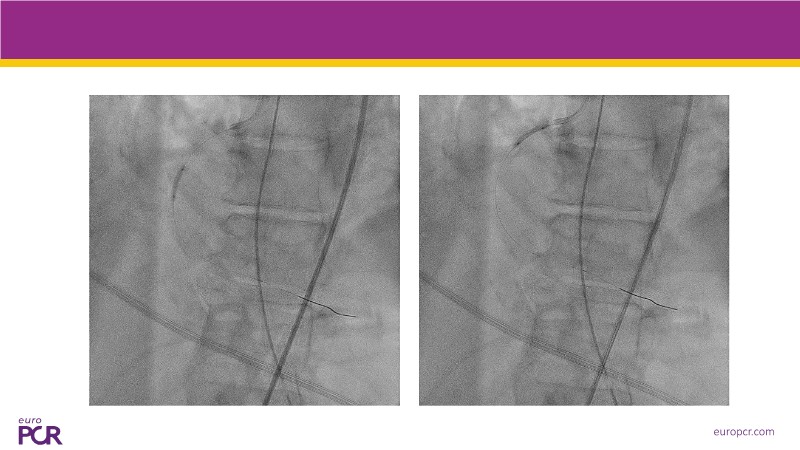

Explore how real-world data and evolving evidence are reshaping IV antithrombotic strategies in complex PCI. This EuroPCR 2025 session brings together urgent clinical cases—including STEMI patients in shock—and highlights key insights from the SMILE registry. Learn how transition protocols from cangrelor to oral P2Y12 inhibitors are applied in practice, compare approaches across Europe and the US, and get a forward-looking perspective on what’s next for IV therapies in 2025. A must-watch for anyone managing high-risk PCI.